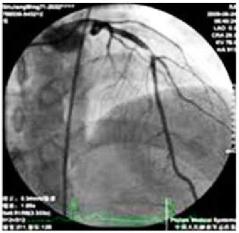

患者接受了急诊冠状动脉造影,显示左前降支近端完全闭塞(LAD),放置2个药物洗脱支架,效果良好。